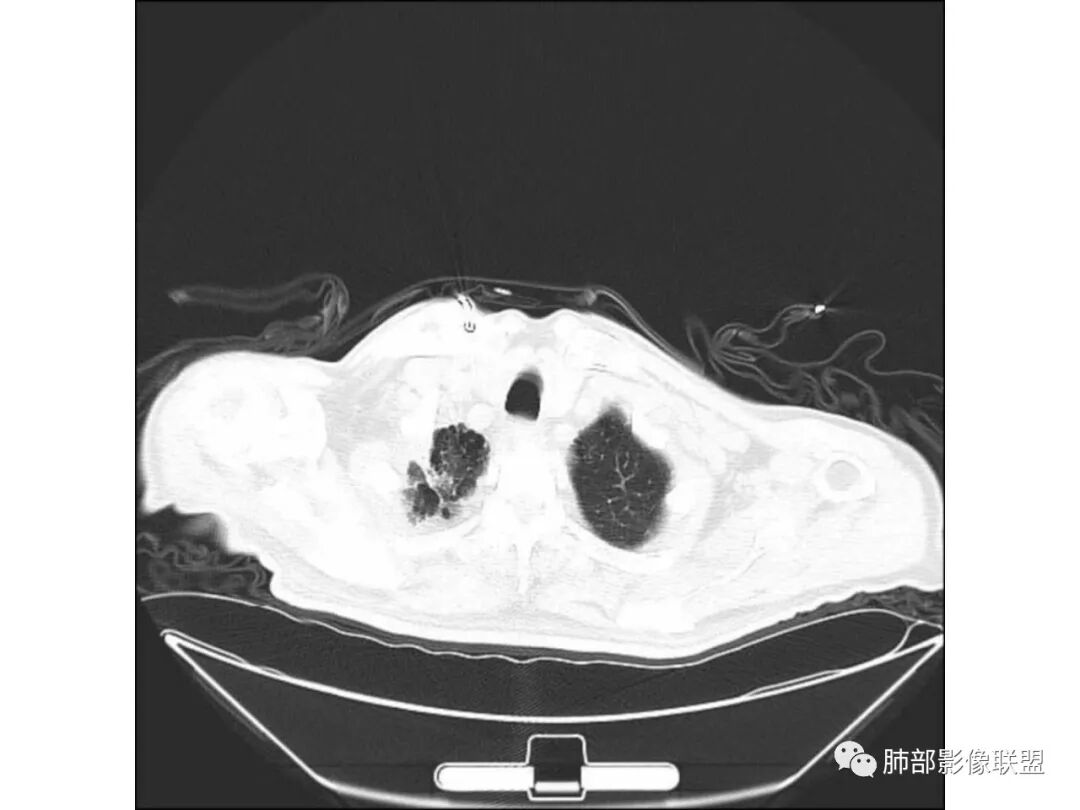

有肺气肿背景,纵隔淋巴结钙化,肺部有纤维化,右肺大片实变,内有融合空洞,未见液平,支气管远端有扩张,部分近段狭窄截断,病灶周边树芽不明显,考虑结核可能大,鉴别腺癌,多为假大空,少有空洞,支气管远端少有扩张所以不符合,肺部感染,多有空洞液平,所以不符合。

老年男性,糖尿病患者。右肺病变,病灶区多发树芽、管状透亮区,考虑为扩张支气管,说明为支气管源性病变。结核?真菌?肺癌?病灶区多发空洞,空洞内坏死不太彻底,树芽征跟增殖结节不明显,结核先不考虑。病灶区晕征不太明显,边界相对清楚,小叶间隔增厚~似呈结节状改变,支气管枯树枝征。最后,肺癌首先考虑,粘液腺癌?鉴别曲霉菌